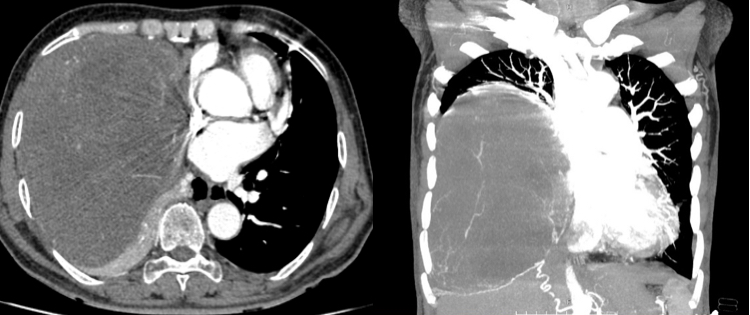

Upon receiving the patient, the doctors quickly resuscitated, relieved the patient's pain, and performed the necessary tests and scans. Through clinical examination and CT scan results of the hip joint, the doctors diagnosed the old woman with a fracture of the trochanteric neck of the right femur, requiring prompt treatment to avoid dangerous complications for the patient.